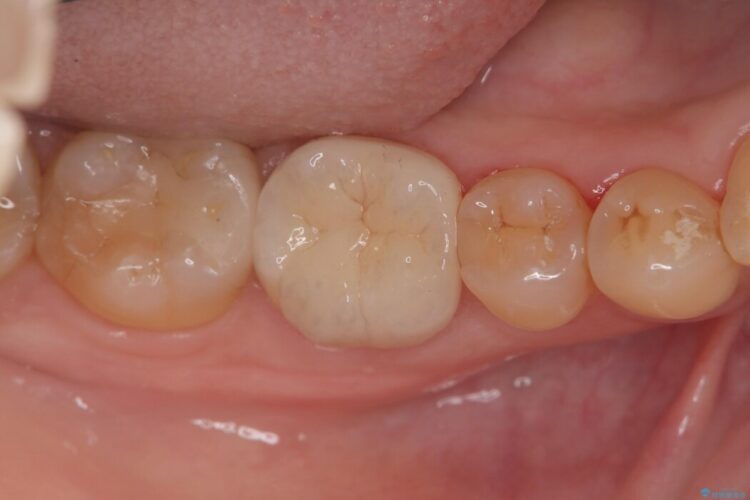

術後の経過は非常に良く、あんなに大きかった膿の袋は消え、健康な骨が再生しているのが確認できました。痛みや腫れも消えて抜歯を免れ、現在は被せ物を入れてしっかりお食事を楽しんでいただけるようになっています。